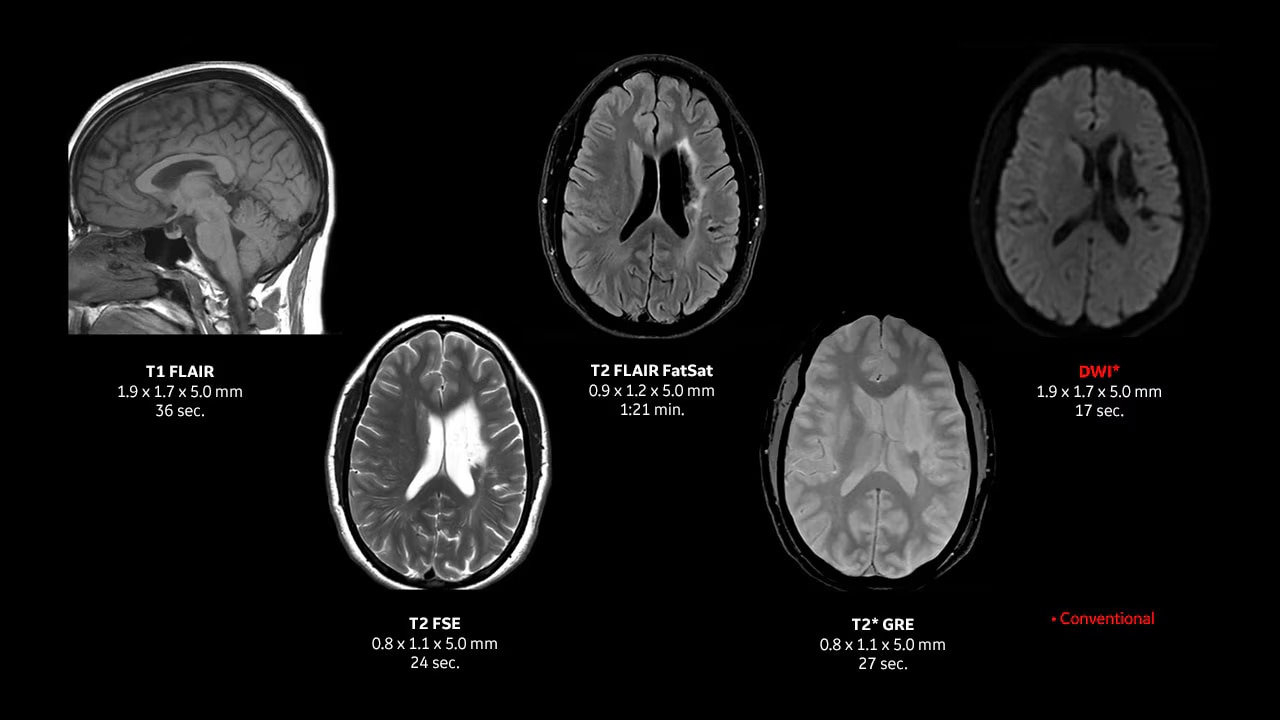

Achieve pin-sharp image quality with pioneering AIR™ Recon DL AI technology.

With access to the latest advanced AI technology, you can scan all anatomies and achieve pin-sharp images. Our pioneering deep learning-based reconstruction algorithm AIR Recon DL accelerates scan time and puts patients at ease.

The improved gradient of up to 80 mT/m, 200 T/m/s provides exceptional results faster and with 146 RF channels, you can ensure uniformity for every result.